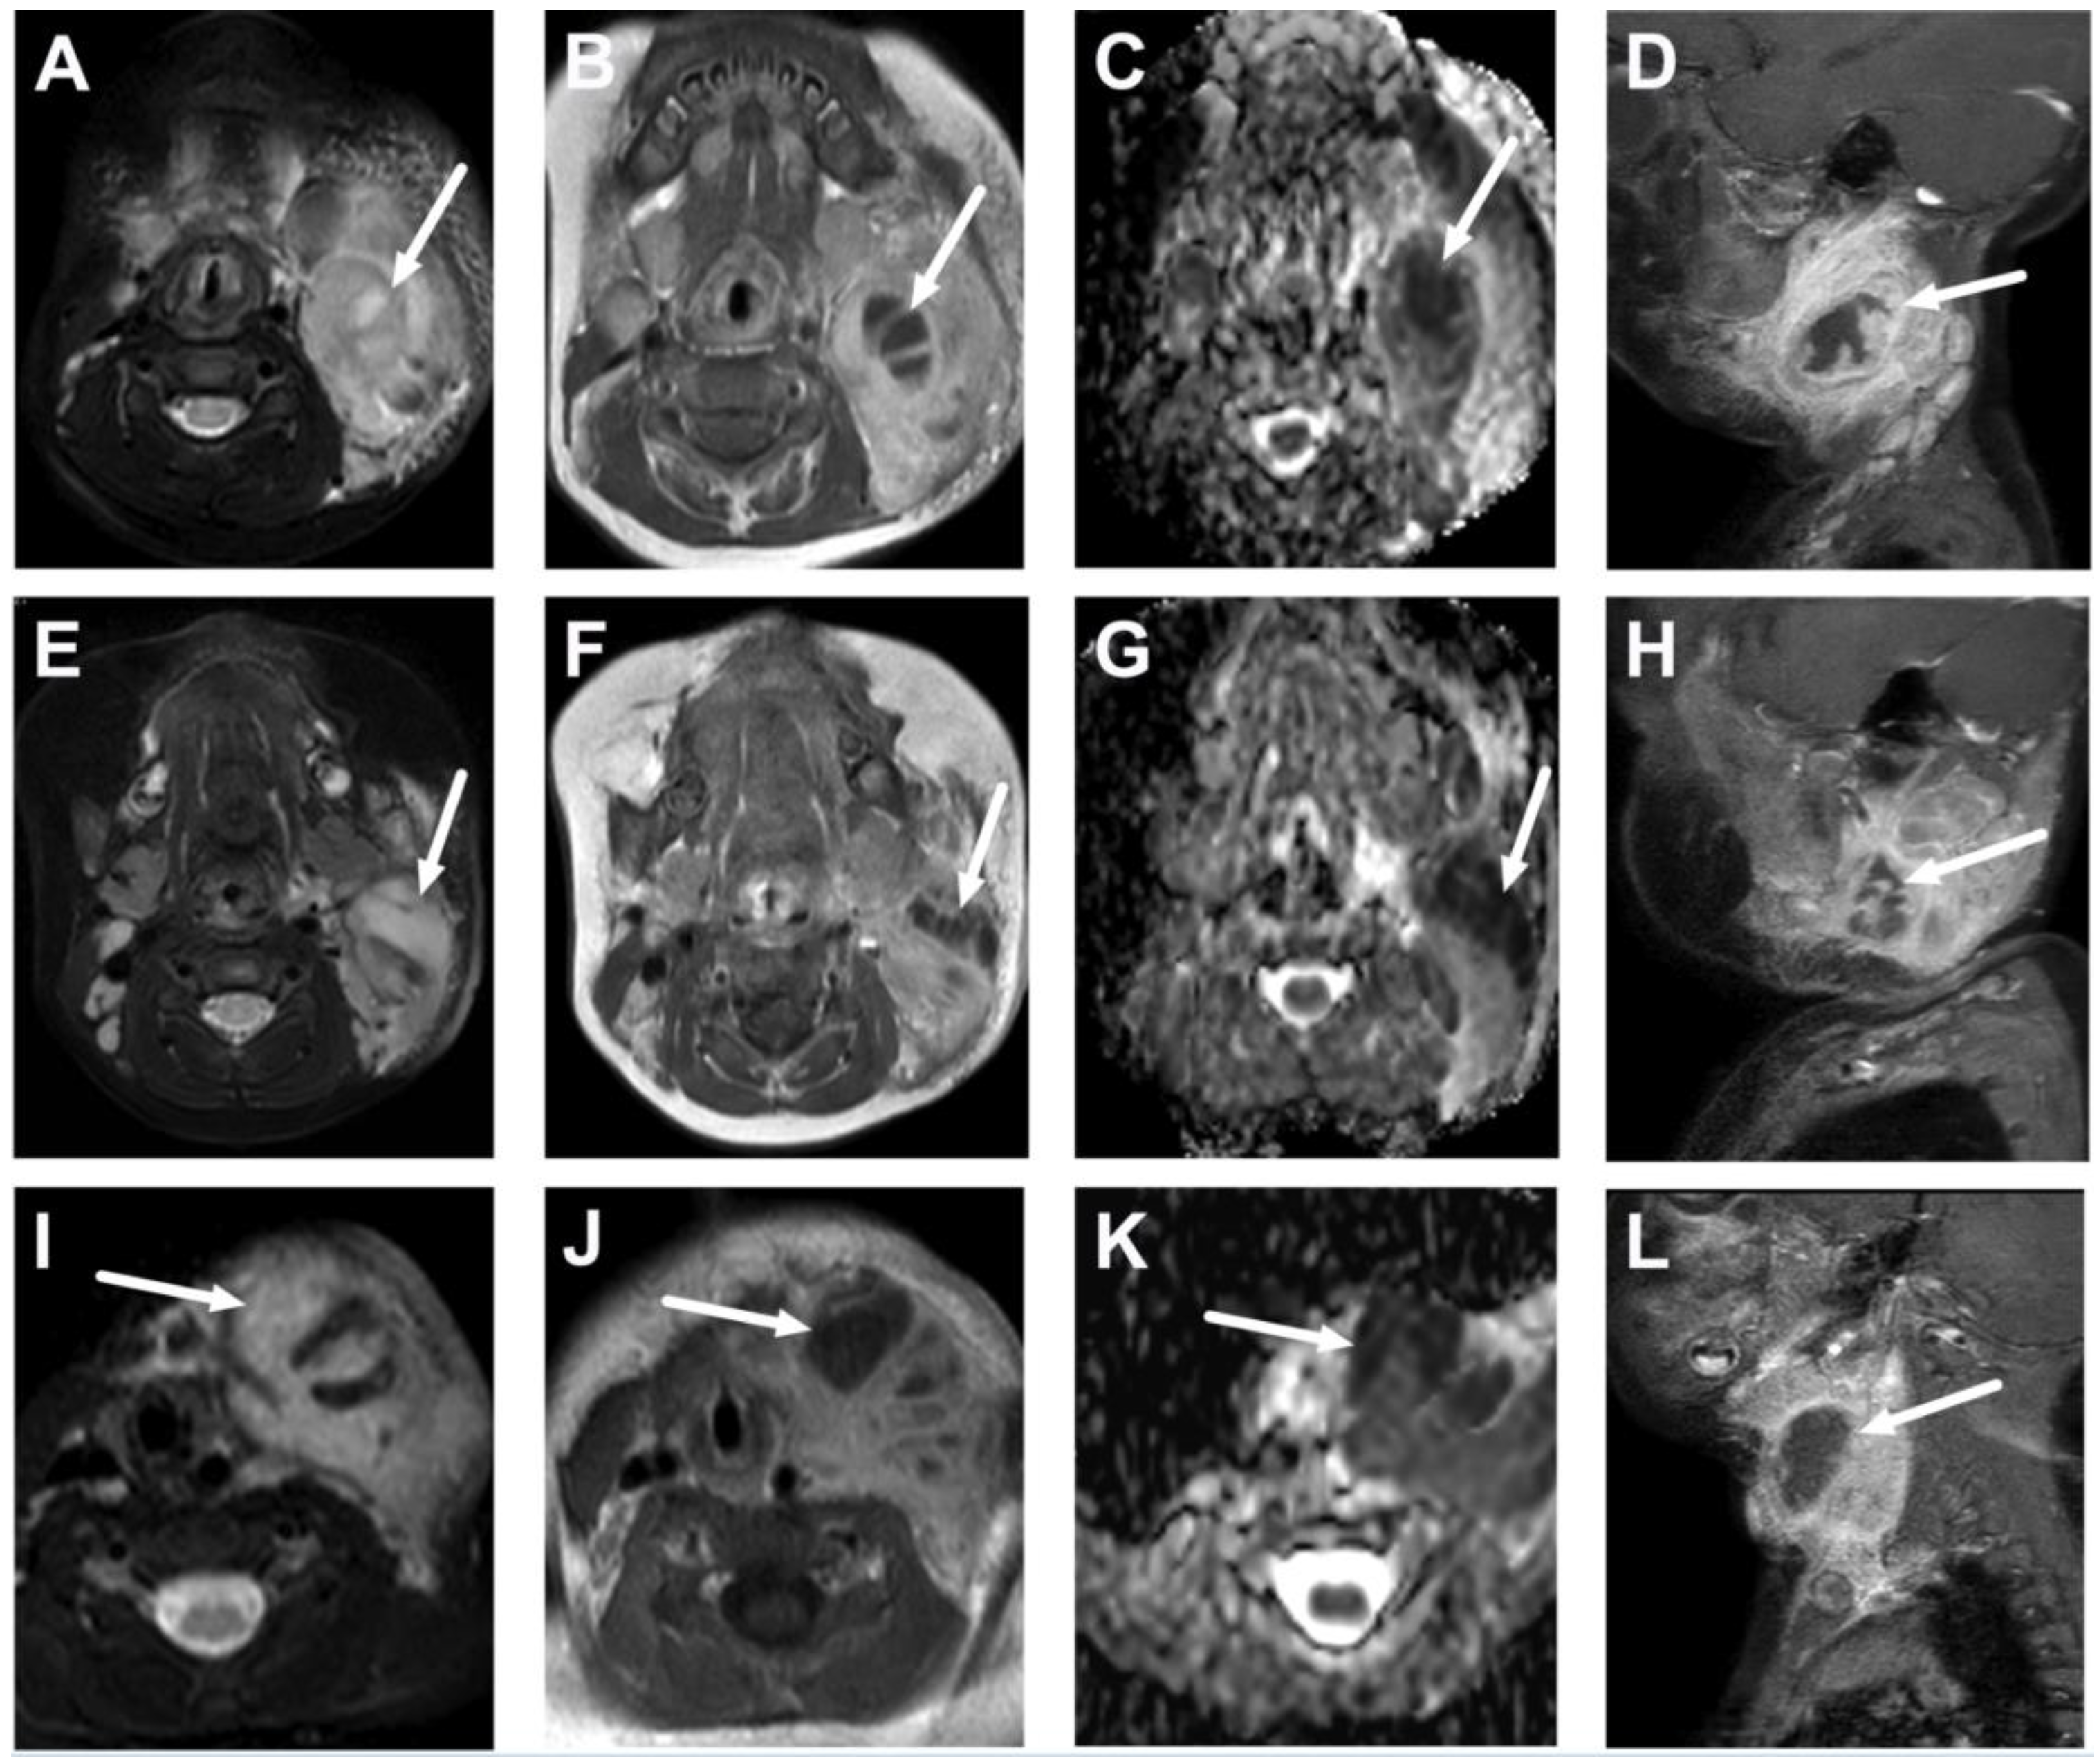

4. Typical Pediatric Deep Neck Infections

4.1. Tonsillitis, Peritonsillar Abscesses, and Parapharyngeal Abscesses

4.2. Retropharyngeal Abscesses and Suppurative Lymphadenitis

4.3. Oral Cavity

4.4. Sialadenitis

5.1. Lymphadenitis with Purulence vs. Necrosis

| Abscess | T1 SE T2 Dixon (water) DWI post-contrast T1 Dixon (water) | Non-enhancing collection with low ADC values enclosed in abnormally enhancing soft tissue edema. | Detection of an abscess usually requires operative consideration and exact abscess location, and extensions are useful in operative planning. | Abscesses may have an intermediate T2 signal content; blood products and/or postoperative status may complicate abscess assessment; necrotic lymph nodes may be misinterpreted as suppurative lymphadenitis. |